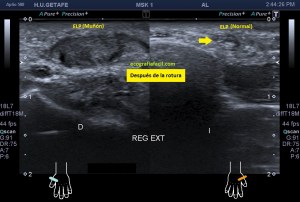

241. Rotura del Extensor Largo del Pulgar. Tercer Compartimento.

Tal como habéis decidido en Insta, voy a proceder a contaros el caso de esta semana. El paciente acude a la cita tarde. No afrontaba la exploración con una actitud positiva, pero la eco te coloca en tu sitio rápido y en este caso, me regaló un caso muy bonito que creo que te va a gustar.

Paciente que acude derivado del traumatólogo por una sospecha rotura del extensor del pulgar. Cuando posicioné al paciente para iniciar la exploración y le hice el interrogatorio habitual, me contó que desde un traumatismo donde se rompió las dos muñecas, tiene una incapacidad para estirar completamente el dedo pulgar a la altura de la interfalángica, no de la metacarpofalángica.

Lo que hace el tercer compartimento nada más desplazarnos hacia distal en el corte axial de la muñeca en su cara extensora y donde visualizamos el tubérculo distal separando ambos compartimentos 2 y 3, lo que hace el tercer compartimento, decía, es cruzarse por encima del dos para buscar diagonalmente su paso y su inserción en la cara dorsal del dedo pulgar. Si no entiendes esta anatomía, no vas a poder entender lo que pasa.

Lo que me llamó la atención fue que la parte superficial del segundo compartimento, correspondiente con el extensor largo del pulgar cruzando por encima del compartimento 2, era que estaba muy hipoecogénica y grande, así que una vez comprobado que los dos tendones del compartimento eran normales, y sabiendo que el tercero pasa por encima para cruzarse buscando el primer dedo, lo que hice fue seguir el tercer compartimento y lo que ví era que estaba situado en su lugar junto al tubérculo de lister, proximalmente, que a su cruce por encima del compartimento dos, estaba hipoecogénico y gordo y que ya en la mano, por donde cruza buscando el primer dedo, no estaba o al menos no estaba íntegro.

En este recorrido encontré un muñón, que se observa perfectamente en longitudinal, y que correspondía con el extensor largo del pulgar a la altura de su recorrido.

3

En esta imagen quiero que te fijes en el segundo compartimento y como el extensor largo del pulgar pasa por encima, los dos tendones del compartimento dos cortados en eje corto y el del tercero, cortado, pero en un corte para-axial. Lo importante es que te fijes en la ecogenicidad de ELP, en la izquierda hiperecogénico, isoecogénico con el segundo compartimento, por tanto normal. En la derecha hipoecogénico y más gordo, patológico.

4

Seguimos avanzando hacia distal, seguimos observando las mismas diferencias en las imágenes comparativas. Imagen justo antes de la rotura.

5

En la rotura el tendón es muy pequeño, pero normal en la izquierda y en la derecha lo es igual de pequeño, pero aplanado y con la pérdida de la ecogenicidad normal.

6

Después de la rotura, avanzando a distal, el tendón retraído, hipoecogénico, mucho más grande que su comparativo contralateral.

7

Corte en eje largo correspondiente a la imagen 6, donde se ve claramente lo que pasa y es definitivo para el diagnóstico final.

En resumen, desde la imagen 3 a la 8 observas el recorrido ecográfico del tendón extensor del pulgar desde proximal hasta distal, pasando por el foco de rotura y terminando con el muñón en axial y en longitudinal según marcan los pictogramas.